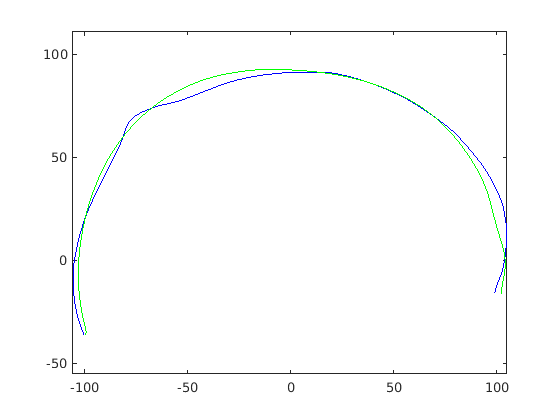

Figure 16 shows examples of the robust ellipse fit for four head profiles. The centre of the ellipse is used in a pose normalisation procedure where the ellipse centre is used as the origin of the profile and the angle from the ellipse centre to the nasion is fixed at -10 degrees. We call this Ellipse Centre - Nasion (ECN) pose normalisation and later compare this to GPA. The major and minor axes of the extracted ellipses are plotted as red and green lines respectively in Fig. 16.

|

|

|

|

Figure 17 shows all 100 profiles overlaid with the same alignment scheme. The median value of major ellipse axis and the ellipse centre-nasion angle differ by 3.6 degrees, so that when the nasion angle is fixed at -10 degrees, the median ellipse angle is -6.4 degrees (cf. -7.4 degrees with manual landmarking of the nasion). We noted regularity in the orientation of the fitted ellipse as is indicated by the clustering of the major (red) and minor (green) axes in Fig. 17 and the histogram of ellipse orientations in Fig. 18. For most people, the major axis of the ellipse is closely aligned with the y-axis (upright), and titled slightly forwards. A minority of heads (9%) in the training sample have their major ellipse axes closer to the vertical (these relatively tall and short heads are known as brachycephalic.) Ellipse axis clustering (relative to the fixed ellipse centre-nasion line) does not appear to be sharply defined. This is because many crania are close to circular in cross-section, making the orientation of these angles sensitive to small changes in shape from one person to the next. Note also the variation at the back of the head due to a variety of hair styles, some of which protrude from under the cap. We limit the region over which we model the cranial shape in order to crop this unwanted data out.